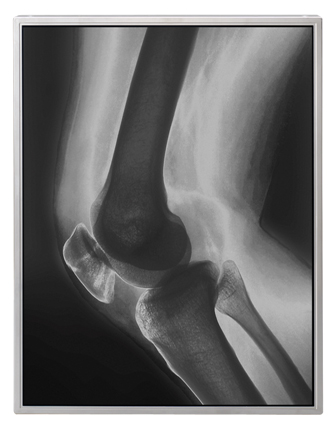

NLTテクノロジー(代表取締役社長:大井進、本社:神奈川県川崎市)はこのたび、X線画像の読影診断をはじめとする医療用途向けに、LEDバックライトを採用した対角54cm(21.3型)の液晶ディスプレイモジュールQXGAカラーモデルおよびモノクロモデル、ならびにUXGAカラーモデルおよびモノクロモデル、計4機種を製品化し、受注を開始します。

医療現場における液晶表示装置の普及に伴い、液晶表示装置に求められる性能はさらに高度化しています。特にここ数年は医療用画像処理技術が飛躍的に進展し、X線画像などのモノクロ画像と、3D-CT(注1)やFusion(注2)などのカラー画像の両方を読影診断できる高輝度タイプのカラー液晶ディスプレイの需要が高まっています。